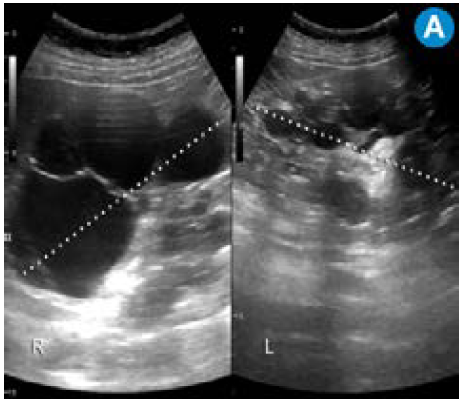

B) CT simple corte coronal: riñones aumentados de tamaño con múltiples quistes. C) Ecografía doppler color: riñón trasplantado sin alteraciones. D) CT simple corte sagital: riñón trasplantado (asterisco), riñón derecho con múltiples quistes (cabeza de flecha) y quiste hepático (flecha). Continúa.

Figura 1: B) CT simple corte coronal: riñones aumentados de tamaño con múltiples quistes. C) Ecografía doppler color: riñón trasplantado sin alteraciones. D) CT simple corte sagital: riñón trasplantado (asterisco), riñón derecho con múltiples quistes (cabeza de flecha) y quiste hepático (flecha). Continúa.

E) CT simple corte sagital: hernia inguinal directa derecha (entre flechas) con pequeña porción de la vejiga dentro del saco herniario (cabeza de flecha).

Figura 1: E) CT simple corte sagital: hernia inguinal directa derecha (entre flechas) con pequeña porción de la vejiga dentro del saco herniario (cabeza de flecha).

Por su alta sensibilidad, disponibilidad y bajo costo, la ecografía renal es el estudio inicial con el que se pueden observar riñones grandes con quistes bilaterales, múltiples y tamaño variable (figura 1); sin embargo, es altamente dependiente del operador y es menos sensible para detectar quistes <1cm que se visualizan mejor en la escanografía o en la resonancia magnética 24. Pese a que en la actualidad no existen criterios estandarizados en estas dos técnicas imagenológicas para el diagnóstico de la PKD, la tomografía computarizada (TC) y la resonancia magnética (RM) son más sensibles para el diagnóstico de los quistes en los casos dudosos, la detección de complicaciones, la valoración de la progresión y la respuesta al tratamiento 25 (figura 2).